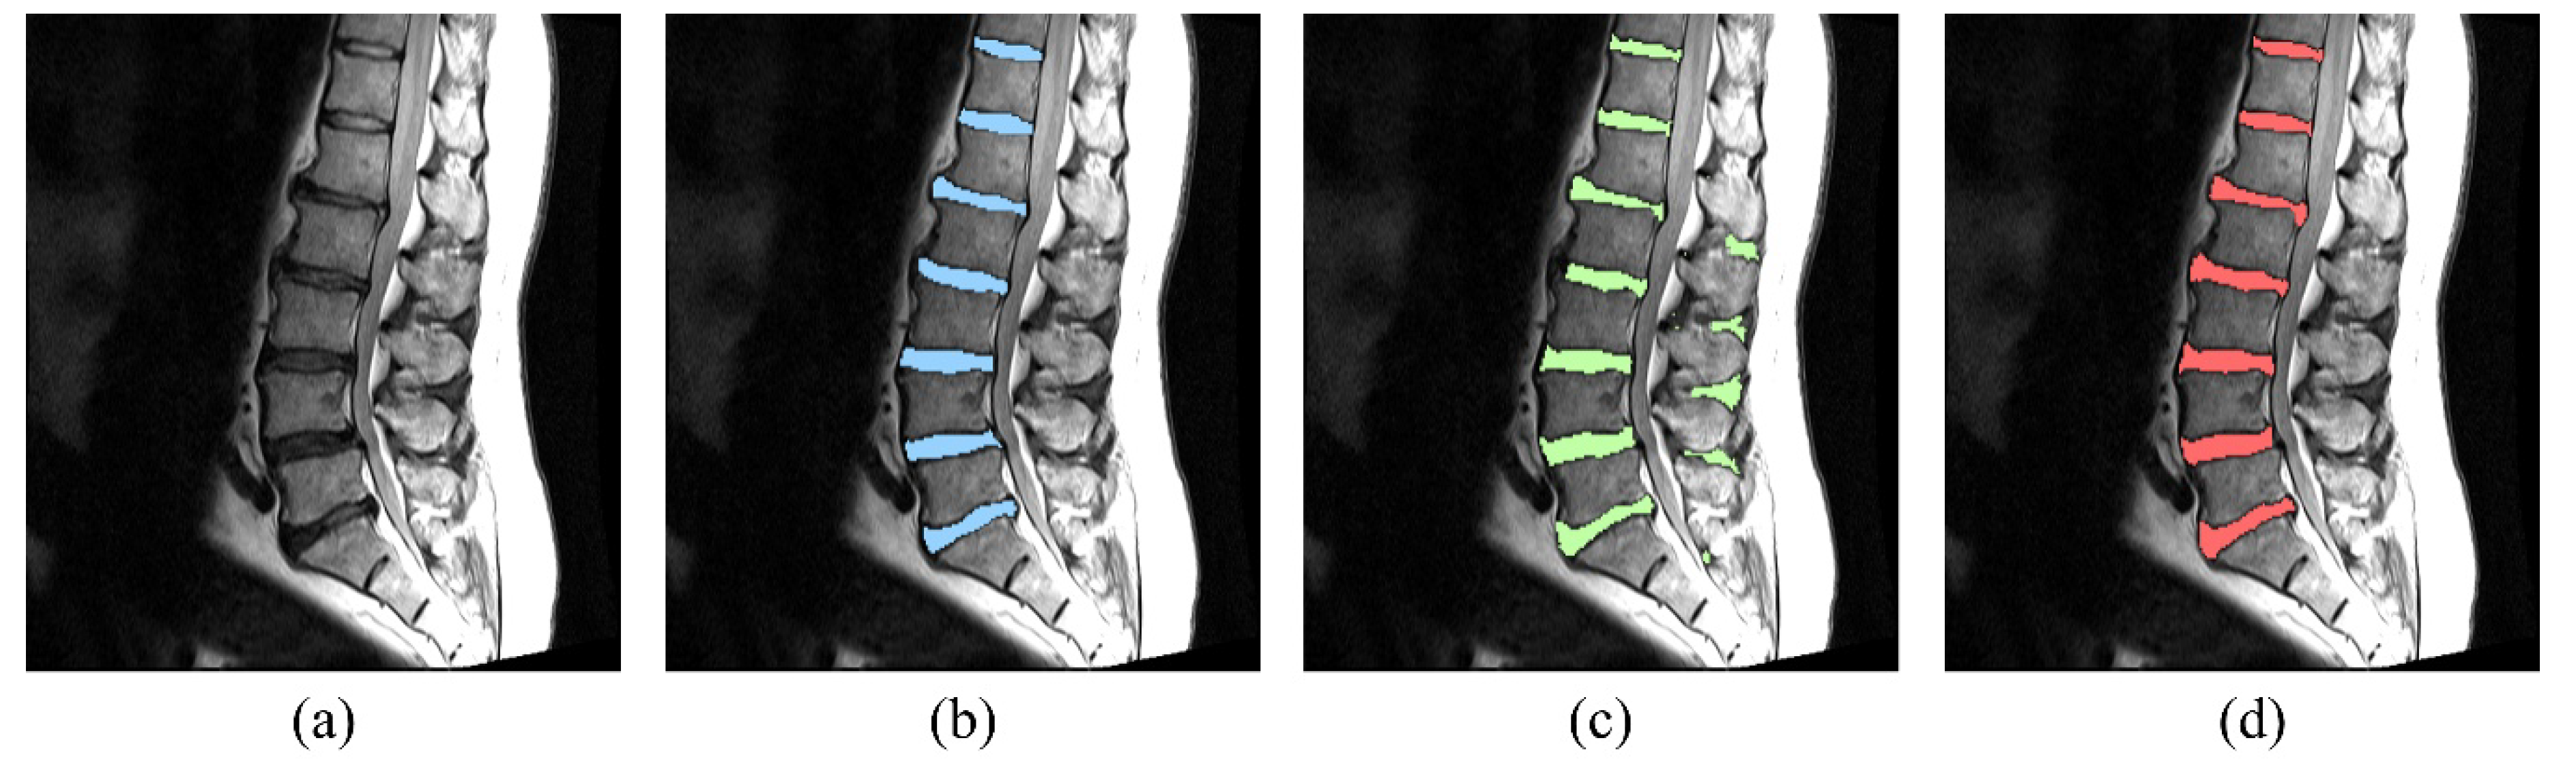

Fine-Grain Segmentation of the Intervertebral Discs from MR Spine Images Using Deep Convolutional Neural Networks: BSU-Net

2.1. Network Design: Boundary Specific U-Network (BSU-Net)